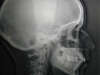

Les radios avant traitement

Les radios